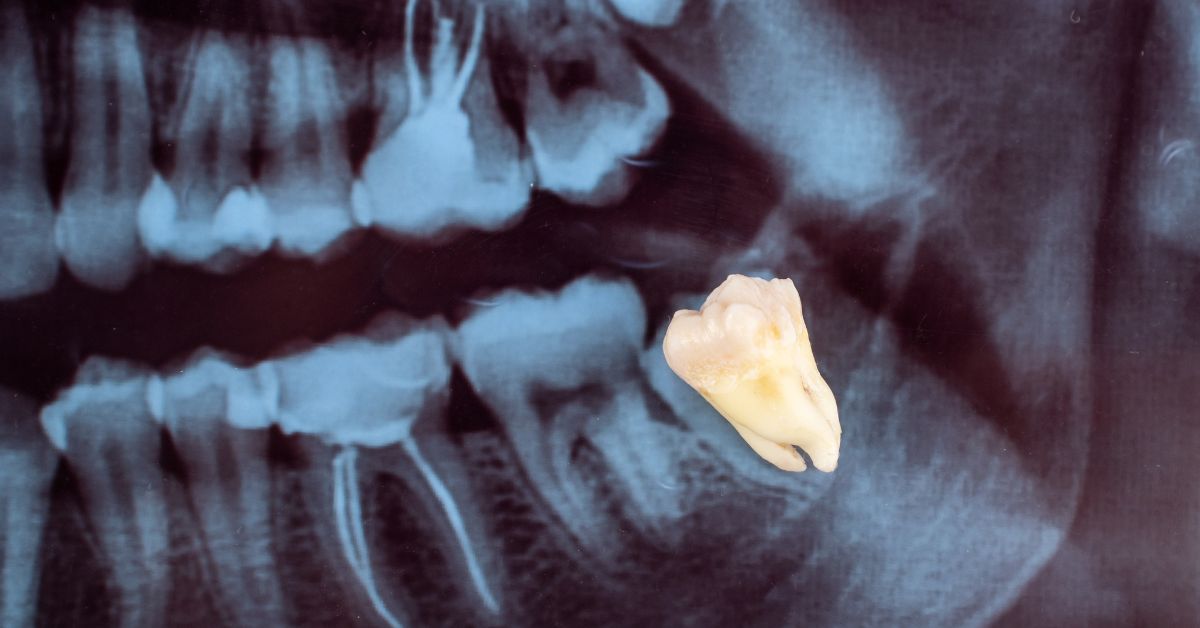

PHD Dental approaches wisdom tooth removal with a planning-first mindset that prioritizes safe access, predictable healing, and a clear understanding of the tooth’s anatomy and eruption pattern. The team evaluates how each wisdom tooth sits relative to surrounding bone, soft tissue, and neighboring teeth so the treatment plan matches the complexity of the case. This clarity builds confidence because patients understand why extraction is recommended and what the procedure is designed to prevent. A well-managed outcome should reduce repeated flare-ups at the back of the mouth, protect adjacent teeth from long-term wear or decay, and support a smoother hygiene routine in a hard-to-reach area.

Impacted wisdom teeth can press against the neighboring second molar, creating hard-to-clean contact points and increasing the chance of decay or gum problems between the teeth. This risk often develops quietly because the area is difficult to see and clean. Patients appreciate learning that extraction is sometimes recommended to protect the healthy tooth in front of the wisdom tooth.

Cavities and Gum Breakdown Between the Wisdom Tooth and Second Molar

Food and plaque can accumulate where the wisdom tooth contacts the second molar, especially when the wisdom tooth sits at an angle. That trap zone can lead to cavities on the back of the second molar or chronic gum irritation in the space between the teeth. Patients often do not notice these problems until imaging or an exam reveals early damage.

Second molars are essential for chewing and long-term bite function, and wisdom teeth can threaten them quietly. Impacted wisdom teeth can create contact points where plaque accumulates and cavities develop on the back surface of the second molar. Extraction protects the second molars by removing the adjacent risk factor that makes decay and gum breakdown more likely.

Preventing Cavities Between Teeth That Are Difficult to Detect Early

Decay between the second molar and an impacted wisdom tooth can develop without obvious symptoms. The location is hard to see and can be missed until the cavity becomes larger and more costly to treat. Patients often feel reassured when the plan focuses on protecting the healthy tooth in front, since that tooth does most of the daily chewing work.